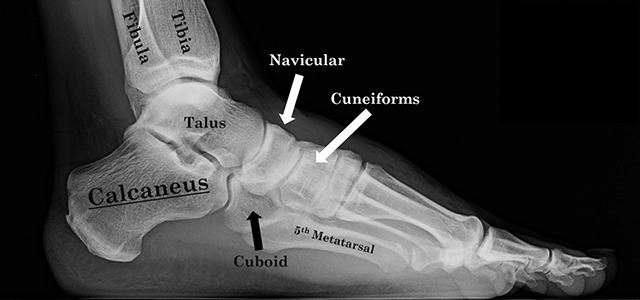

what are the tarsals?

Tarsals – a set of seven irregularly shaped bones. They are situated proximally in the foot in the ankle area.

what is the talus?

the bone that articulates with the tibia and fibula to make the ankle joint

what is the name of the heel bone? which set of bones does it belong to?

calcaneus - tarsals

what are metatarsals?

Metatarsals – connect the phalanges to the tarsals. There are five in number – one for each digit.

what are the phalanges?

Phalanges – the bones of the toes.

Each toe has three phalanges – proximal, intermediate, and distal (except the big toe, which only has two phalanges: proximal and a distal one).